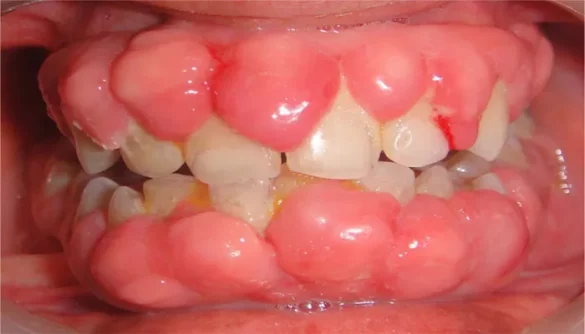

Hyperplasia of the gums, also known as gingival hyperplasia or gingival overgrowth, is a condition characterized by an abnormal increase in the size of the gum tissue. This enlargement can affect oral health, aesthetics, and comfort.

Gingival hyperplasia refers to the excessive growth of gum tissue, often leading to swollen, thickened, or protruding gums.

The condition may affect a specific area of the gums or extend to the entire gumline. It can occur in individuals of all ages but is more common in certain populations based on the underlying causes.

Hereditary Gingival Fibromatosis (HGF) is a rare genetic disorder that causes slow but progressive gum enlargement. The condition is usually evident from a young age and may require surgical intervention to manage.

Non-inflammatory overgrowth.

Firm, fibrotic gum tissue.

Often associated with other dental anomalies.